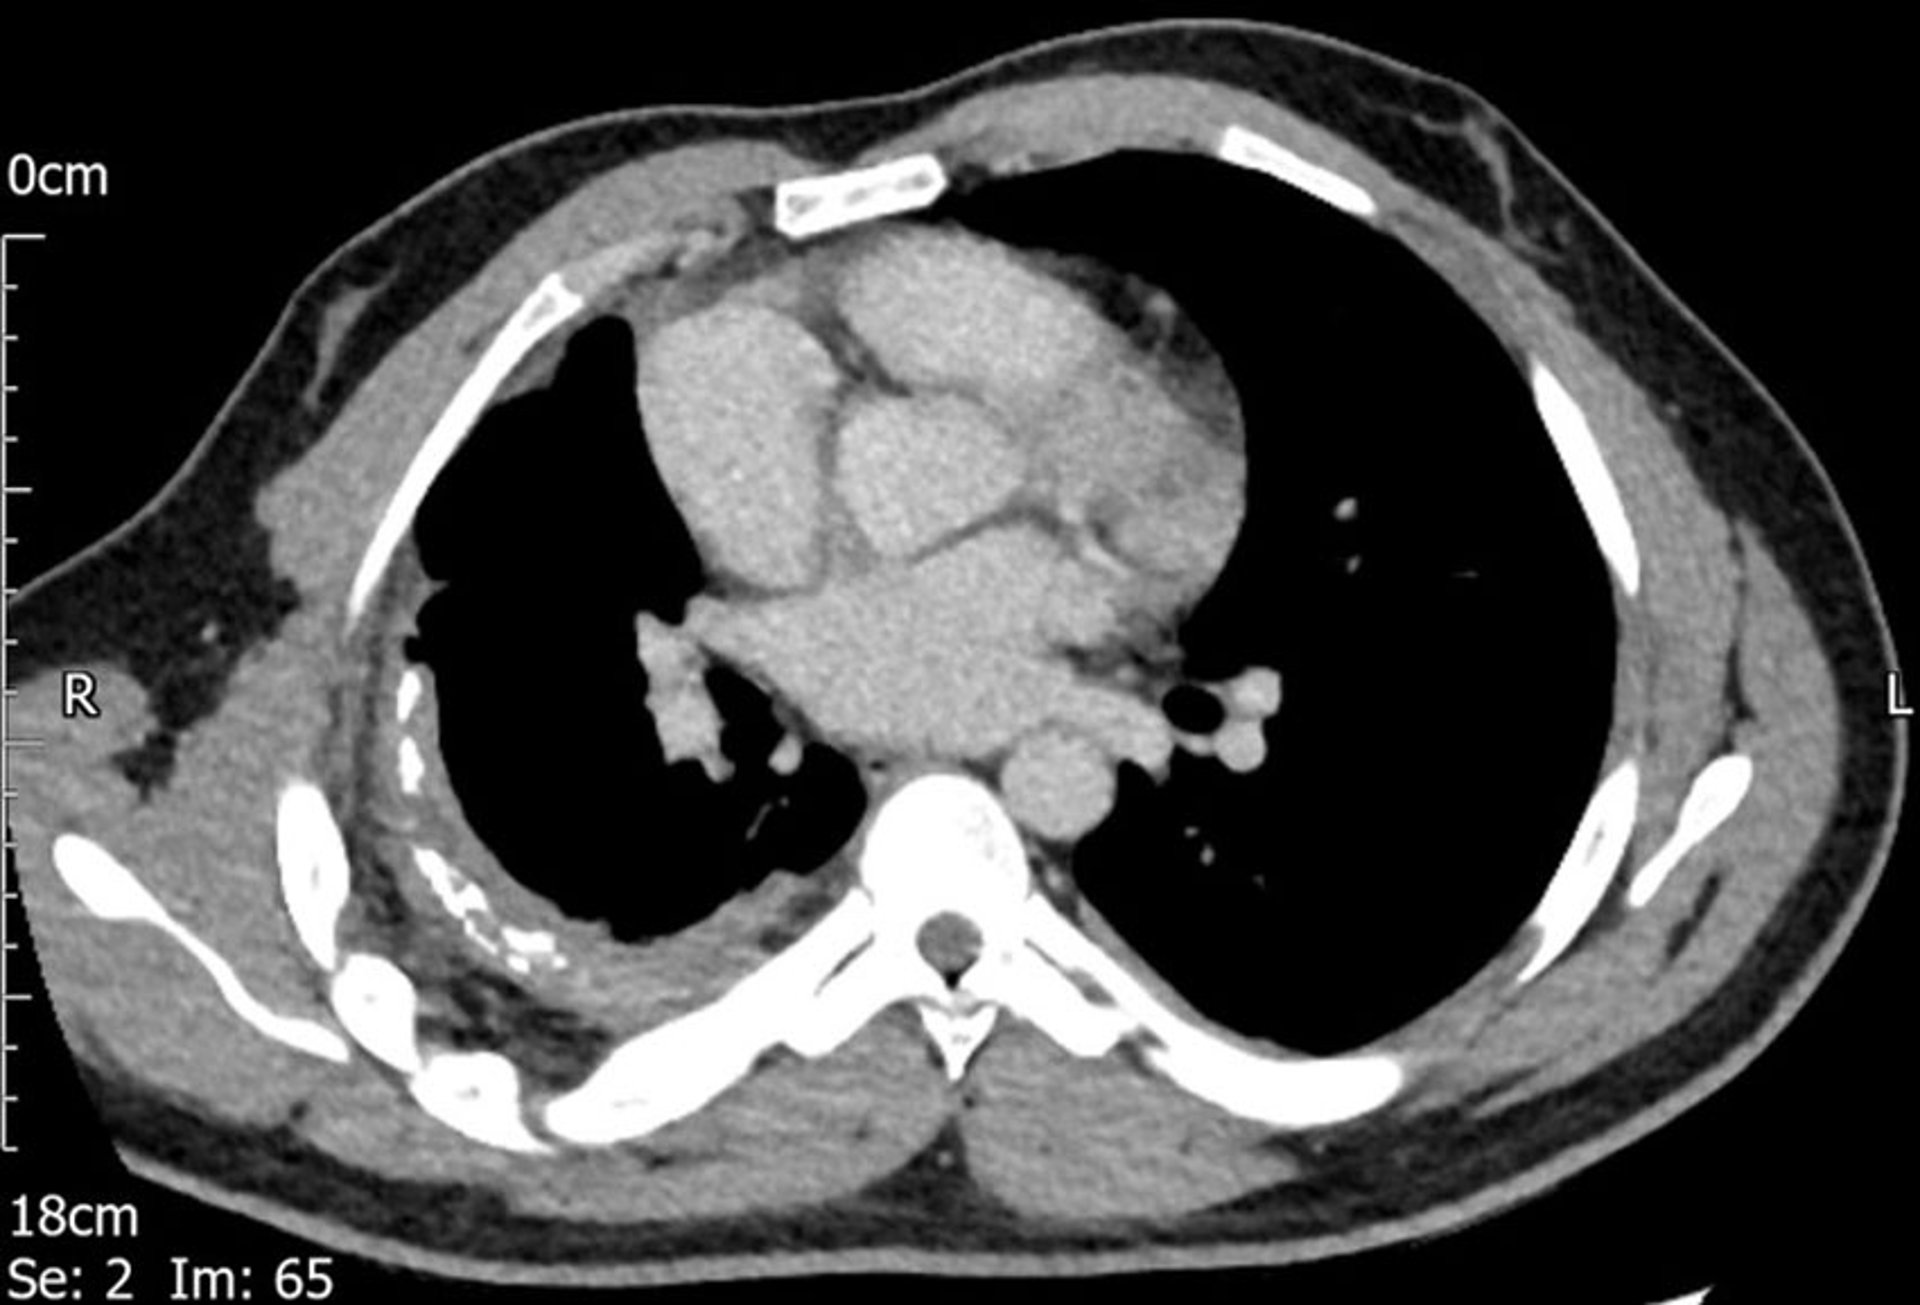

CT扫描显示右侧胸膜增厚。

图像由Najib M.提供。Rahman, BMBCh MA (oxon) DPhil.